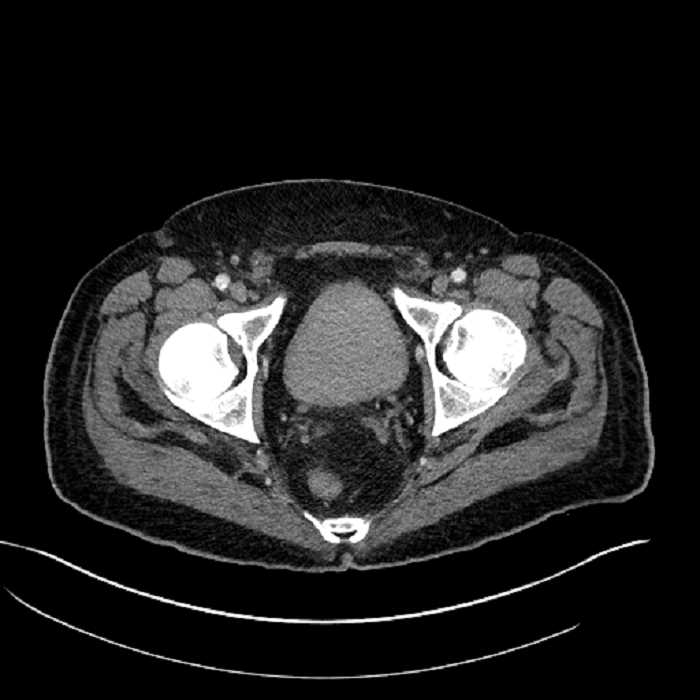

• Large fluid density structure in hepatic segments 7 and 8 measuring 10 x 7 x 7 cm with internal septation and circumferential ill-defined low density compatible with edema

• Peripherally enhancing subcapsular collections along the anterior margin of the left hepatic lobe measuring 3 x 1 cm and 2 x 1 cm

• High grade stenosis of the left common iliac artery, with the left internal and external iliac arteries remaining patent

Acute sigmoid diverticulitis complicated by a small contained perforation and a large abscess in the right hepatic lobe. Additional small subcapsular abscesses along the anterior margin of the left hepatic lobe.

Additionally, loss of the normal fat plane between the peridiverticular collection and adjacent thickened loops of small bowel raises the potential for an enterocolonic fistula.

High grade stenosis of the left common iliac artery. The left external and internal iliac arteries are patent.

Hepatic abscess showing the double target sign with low density internally surrounded by a thin inner enhancing rim (red arrow) and ill-defined outer low density rim (yellow arrow). Blue arrow indicates an internal septation. Red arrows: additional smaller subcapsular abscesses. Red arrow: focal contained perforation associated with diverticulitis.